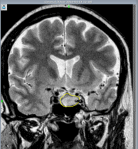

Рисунок Магнитно-резонансная томограмма головного мозга в коронарной плоскости: аденома гипофиза

Аденомы гипофиза на Т1 ВИ – визуализируются как зоны со сниженным по сравнению с остальной тканью аденогипофиза сигналом, на Т2ВИ – как зоны с повышенным сигналом. При внутривенном контрастировании аденомы накапливают контрастное вещество и можно более детально оценить структуру опухоли.